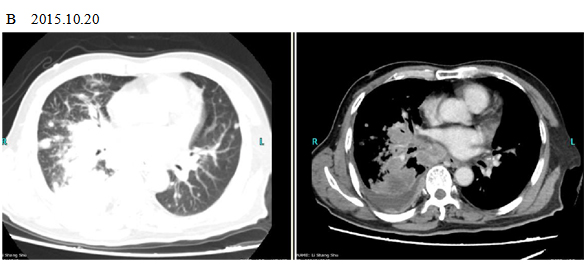

A 66-year old male patient with a smoking history was received by the Outpatient Department on September 14, 2015 due to “coughing for more than one month”. Main symptoms included a dry cough, a small amount of white phlegm, but freedom from fever, chest pains, bloody sputum, and any other discomfort. Stage IV-lung cancer is associated with anorexia and a loss of nearly 10 pounds. The patient had a poor constitution in the past, with a history of “acute hepatitis”, “type-2 diabetes” and “obsolete pulmonary tuberculosis”. The patient was accepted in the Department of Respiratory Medicine on September 15. The results of a lung CT scan indicated a “space occupied for posterior basal segment of right inferior lung and enlarged for mediastinal lymph nodes”. The patient was approved for a CT- guided transthoracic needle biopsy, immunohistochemistry, EGFR gene mutation detection, and systemic metastases assessment. He was diagnosed as “primary lung cancer, right lung adenocarcinoma, T4N3M1B (lung, pleura and brain), and stage-IV EGFR Exon 19 deletion mutation (Fig. 1A and Fig. 2A)”.

The patient checked for further treatment on November 23, 2015. A pre-chemotherapy assessment was made and the results showed multiple bone metastases and multiple enlarged lymph nodes in the left shoulder blade, the fourth lumbar, the right iliac bone and other locations. Performance status (PS) was only one point. Pemetrexed Disodium (500 mg/m2 d1) + Carboplatin (AUC 5 d1) + Bevacizumab (7.5 mg/Kg d1) was administered beginning November 26, 2015 for the chemotherapy treatment and supportive therapy was provided, such as, dehydration, reduction of intracranial pressure, promotion of bone repair, pain relief, and waist protection. After discharge, the coughing basically disappeared and the dizziness, backaches, and hemiparesthesia of the left side were significantly improved. Patient emotional state and sleep quality was significantly improved. It was basically normal after a routine blood examination. A second chemotherapy treatment was successfully completed on December 18 (the program is idem). The patient returned to the hospital on January 6, 2016 and was proposed for a third chemotherapy. The pre-chemotherapy assessment showed that the measurable, targeted right lung lesion had decreased (3.2 mm, with a rate of decrease 44.8 %) (Fig. 1D). Lymphangitis carcinomatosa was significantly decreased and right frontal nodulus lesions were reduced significantly (Fig. 2C). No new lesions were found. Efficacy was assessed as partial relief (PR). A third and fourth chemotherapies were completed on January 9 and January 30, 2016. Efficacy was re-assessed as PR (Fig. 1E) with lung CT review as an outpatient on February 11. Since then, the patient had been subjected to a combined administration program of pemetrexed disodium (500 mg/m2 d1) + bevacizumab (7.5 mg/Kg d1) for continued chemotherapy. A lung CT and a cranial MRI were peformed on April 16. The results showed that the control of lung lesions and intracranial lesions were basically the same as before (Fig.1F and Fig. 2D). The patient had no cough, backaches, or hemiparesthesia and the quality life significantly improved. PS was decreased to zero.